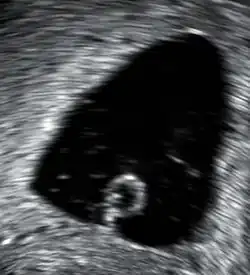

In the case of blood loss, pain, or both, transvaginal ultrasound is performed. If a viable intrauterine pregnancy is not found with ultrasound, blood tests (serial βHCG tests) can be performed to rule out ectopic pregnancy, which is a life-threatening situation.[107][108]

A miscarriage may be confirmed by an obstetric ultrasound and by the examination of the passed tissue. When looking for microscopic pathologic symptoms, one looks for the products of conception. Microscopically, these include villi, trophoblast, fetal parts, and background gestational changes in the endometrium. When chromosomal abnormalities are found in more than one miscarriage, genetic testing of both parents may be done.[109]

Ultrasound criteria

A review article in The New England Journal of Medicine based on a consensus meeting of the Society of Radiologists in Ultrasound in America (SRU) has suggested that miscarriage should be diagnosed only if any of the following criteria are met upon ultrasonography visualisation:[110]

| Crown-rump length of at least 7 mm and no heartbeat. | Crown–rump length of less than 7 mm and no heartbeat. | [110][111] |

| Mean gestational sac diameter of at least 25 mm and no embryo. | Mean gestational sac diameter of 16–24 mm and no embryo. | [110][111] |

| Absence of embryo with heartbeat at least 2 weeks after an ultrasound scan that showed a gestational sac without a yolk sac. | Absence of embryo with heartbeat 7–13 days after an ultrasound scan that showed a gestational sac without a yolk sac. | [110][111] |

| Absence of embryo with heartbeat at least 11 days after an ultrasound scan that showed a gestational sac with a yolk sac. | Absence of embryo with heartbeat 7–10 days after a scan that showed a gestational sac with a yolk sac. | [110][111] |

| Absence of embryo at least 6 weeks after last menstrual period. | [110][111] | |

| Amniotic sac seen adjacent to yolk sac, and with no visible embryo. | [110][111] | |

| Yolk sac of more than 7 mm. | [110][111] | |

| Small gestational sac compared to embryo size (less than 5 mm difference between mean sac diameter and crown-rump length). | [110][111] |